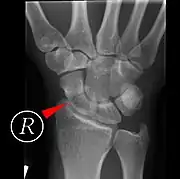

Scaphoid fractures may be difficult to diagnose via plain x-ray. A repeat x-ray may be required at a later date, as might cross-sectional imaging via MRI or CT scan.[6]